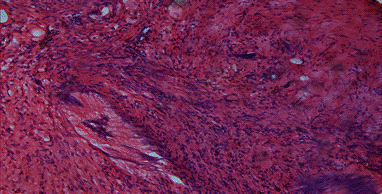

glandulous hyperplasia a plenty of differently - shaped structures covered by flatly or cubed epithelium with eosinophil cytoplasm are seen. Page 6.

6. Differently - shaped structures.

6. Flatly celled metaplasia.

stroma is party swollen with a lot of vessels and infiltration of leucocytes, lymphocytes and plasmacytes. Page 6.

6. The stroma is party swollen with a lot of vessels.